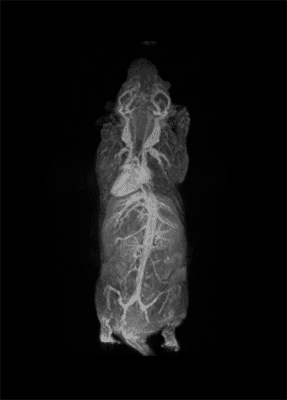

Molecular imaging aims at the visualization of molecules or molecular events that occur at the cellular level. Clearly it also allows the possibility of looking inside the biochemical pathway at the cellular level and therefore enables us to look at the onset of diseases well before they are resolved into structural change. This is what we are currently doing with it.

Molecular imaging is really a truly interdisciplinary science. It needs biologists in order to find biomarkers related to a specific disease. It needs chemists that will design and synthesize the proper probe in order to target this biomarker of interest. It needs imaging scientists in order to take maximum advantages from available imaging modalities. Of course it also requires physicists and engineers to develop the proper scanner with the sensitivity and specificity.

I think the future of molecular imaging is very bright. The possibility to look inside the body with eye spatial resolution and to look at the biochemical processes that are related to the onset of the diseases open a beautiful scenario in order to fit all the terrific achievements that have come from biology and from molecular medicine.

To some extent I think we are on the top of an iceberg where the potentiality can be dramatically improved by looking at small objects, such as live cells, because in principle we always aim to go down to the single cell information.